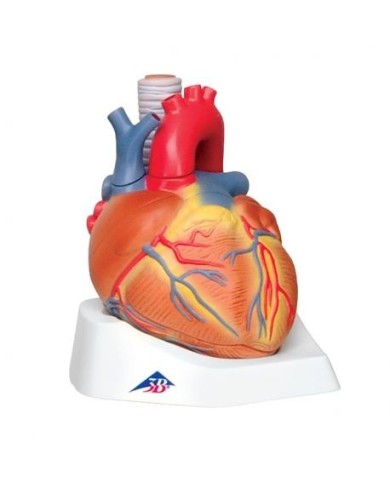

Modello di cuore di alta qualità scomponibile in 5 parti

Modello di cuore di alta qualità scomponibile in 5 parti

La parete anteriore del cuore è staccabile per poter vedere i ventricoli.

Modello anatomico di cuore, ingrandito 2 volte, su cavalletto